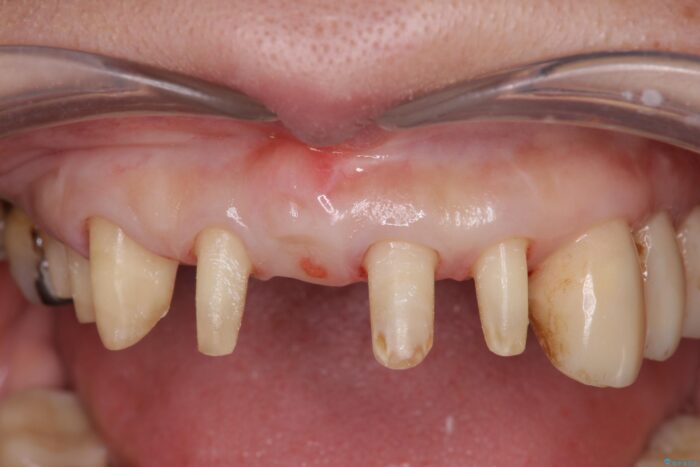

長年、他院にて定期管理および歯周病治療を継続されていたものの、突然多数の抜歯を宣告されたことで治療方針に疑問を抱かれ、当院へ歯周病治療のご相談に来院されました。

検査の結果、歯周ポケットの測定値は4-6mm程度の値が全顎にわたって認められ、中等度歯周病の状態です。

歯を今後残し、歯周病の状態を改善するため、歯槽骨の再生治療をおこなったのち、歯周ポケットの除去、セラミックブリッジの製作を行う治療計画を実行していきます。